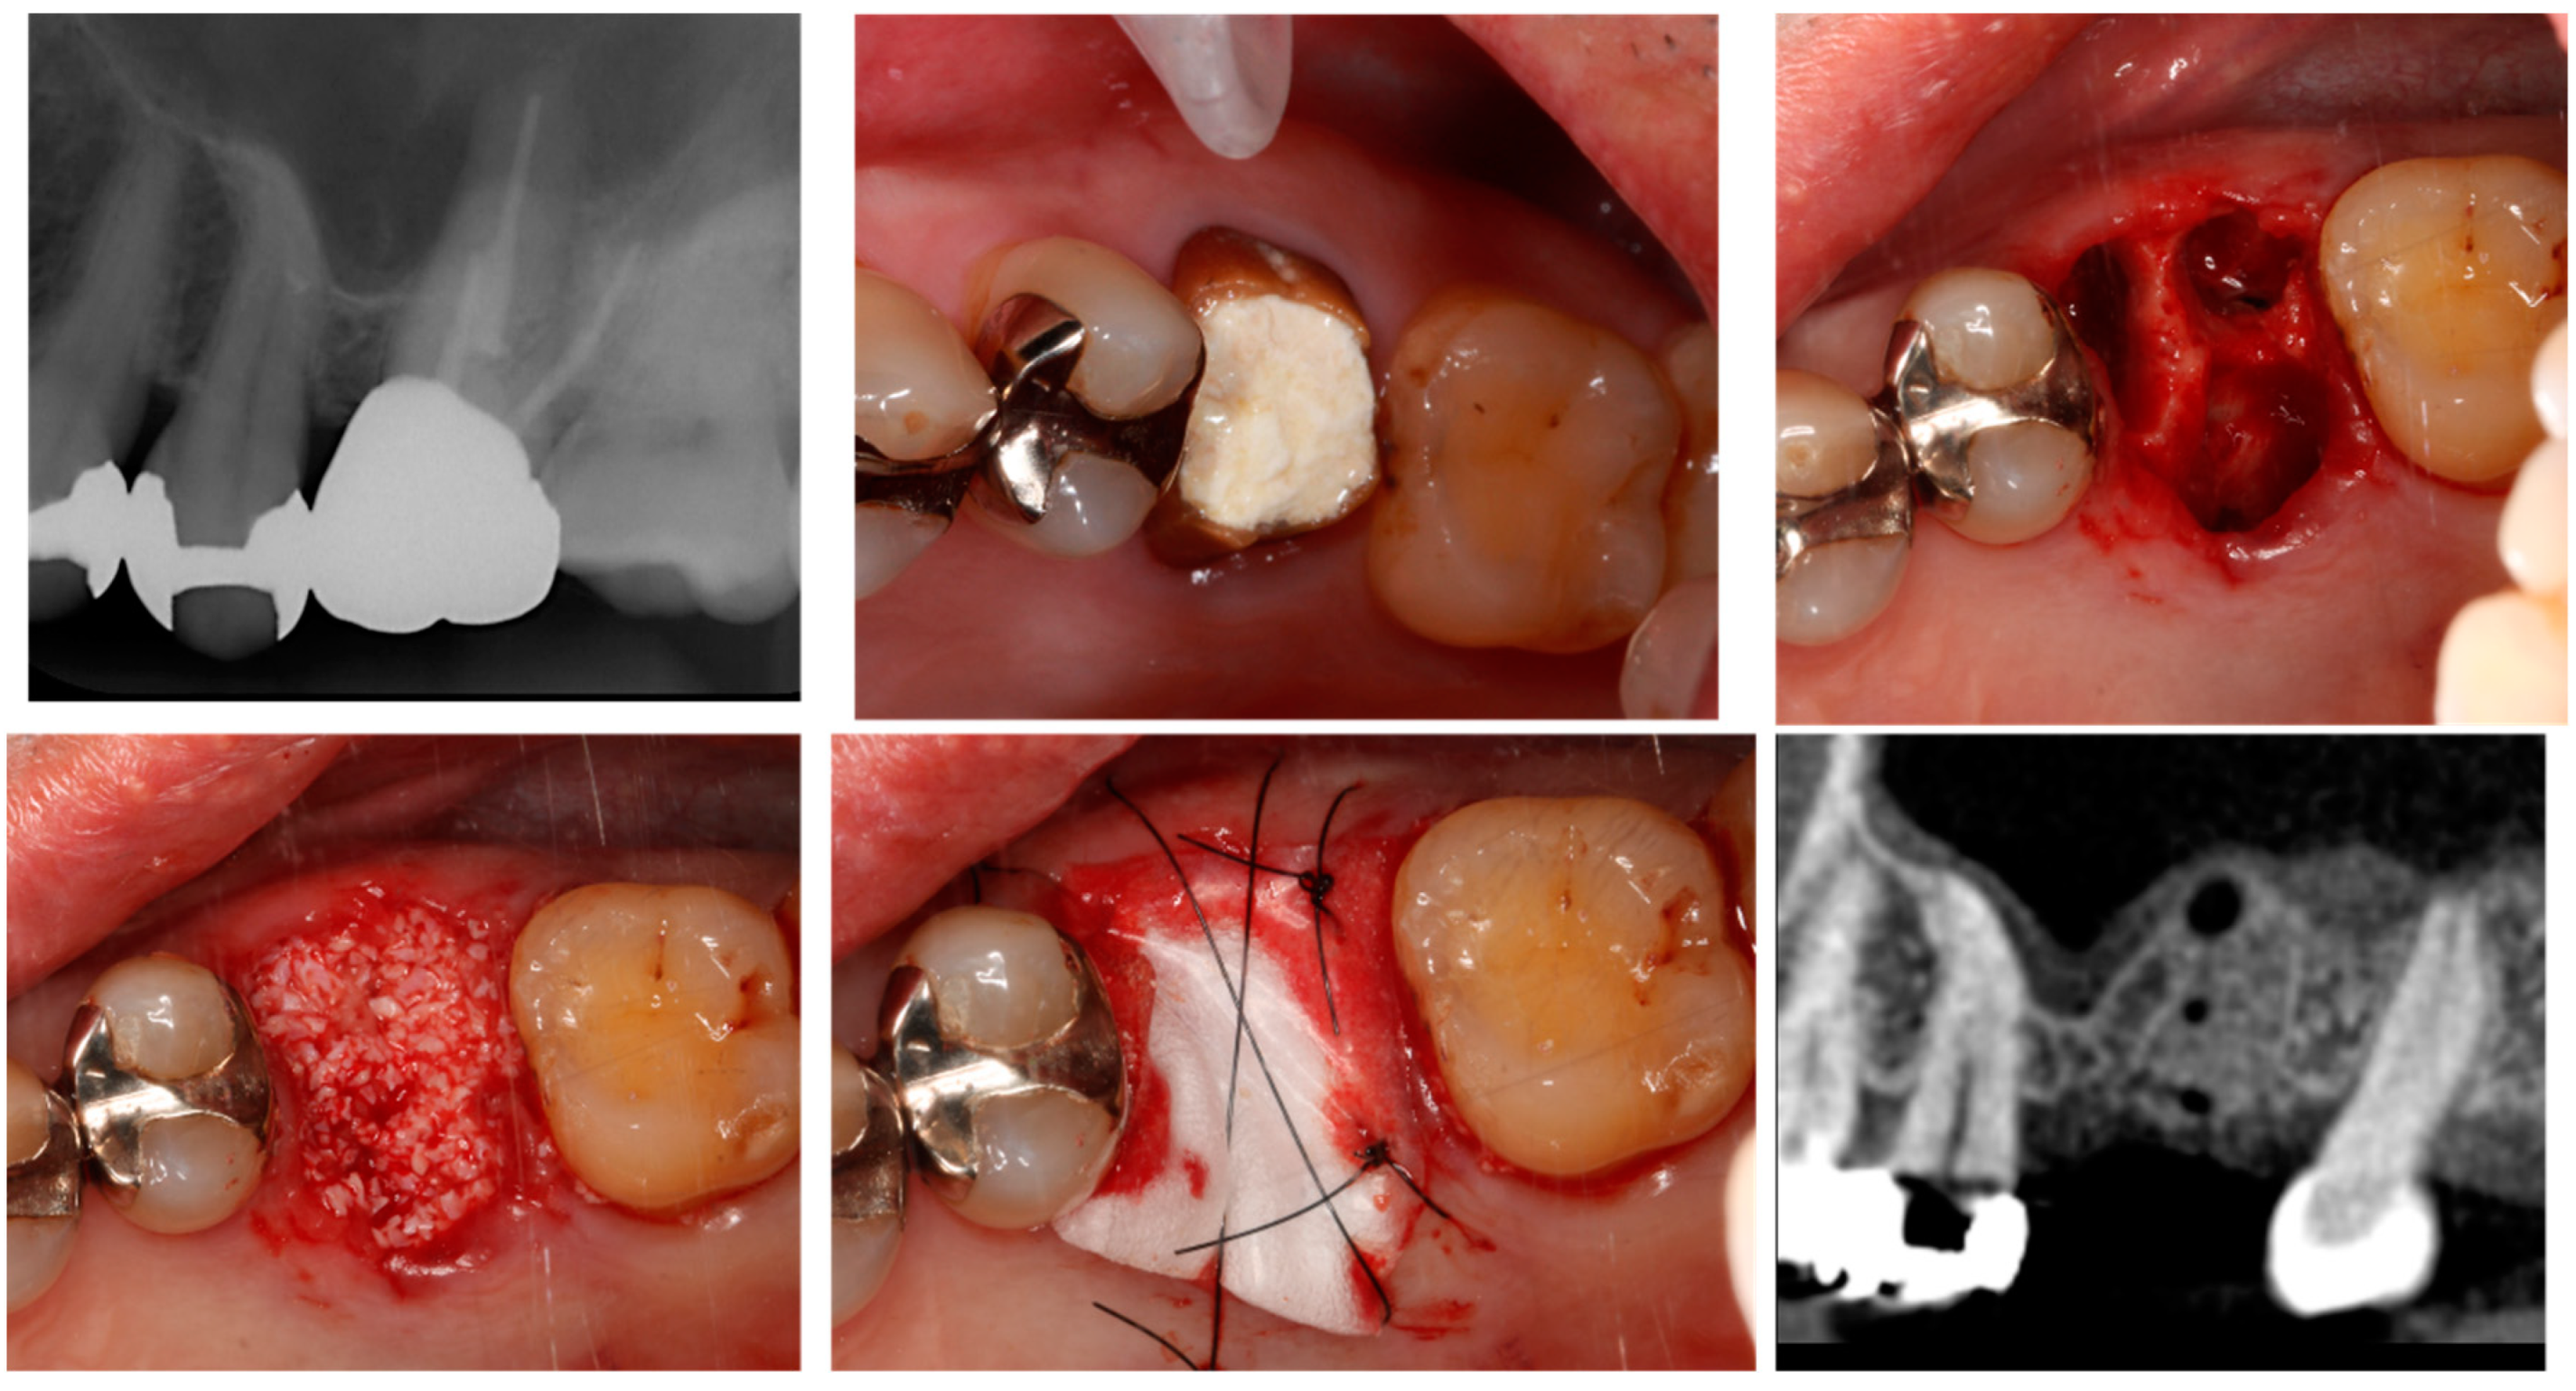

4.1. Alveolar Ridge Preservation

4.1.1. Efficacy of Alveolar Ridge Preservation and Associated Complications

4.1.2. Selection of Bone Grafting Materials in ARP